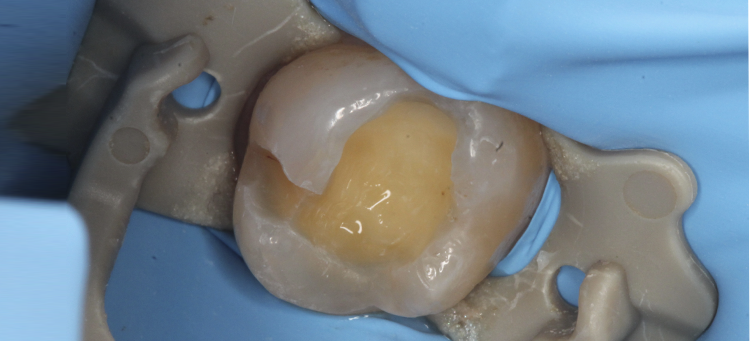

Лечение кариеса зубов